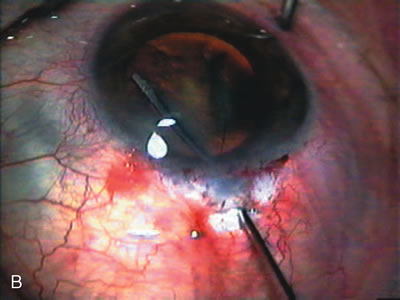

The inflammation associated with lens extraction at any site usually causes complete failure of a marginal functioning bleb. In addition, pressure reduction by medical means is usually minimal in these recalcitrant cases, and combined surgery is indicated. In the past, these cases were approached with large-incision ECCE, clear corneal cataract incision, and bleb revision. Drawbacks included those mentioned earlier for large incision clear corneal cataract extraction, and bleb revision is often associated with conjunctival buttonholes, wound leaks, subconjunctival hematoma, destruction of friable sclera, and associated hypotony. With the advent of modern-day cataract surgery, a phacotrabeculectomy is often possible adjacent to the failed filter (Fig. 7). The ability to combine cataract extraction with implant and filtration surgery all through the same small incision has greatly improved outcomes for patients with marginal preoperative filters. There are several other viable options in this case. If the surgeon elects to remove the cataract through a temporal clear corneal incision, the bleb may be revised or a new adjacent filter fashioned. As mentioned earlier, revising a failed filter is technically challenging. If the surgeon believes it is not feasible to revise the filter or fashion a new one, a glaucoma drainage implant is a reasonable option combined with temporal lens extraction.172

Fig. 7. Phacotrabeculectomy adjacent to a failed filter in cataractous eye. The ability to combine small-incision cataract extraction with trabeculectomy all through the same incision adjacent to the failed filter allows the surgeon to work in a familiar superior area. Avoiding incisions into the existing bleb decreases conjunctival buttonholes, hypotony, operating room time, and subconjunctival bleeding. A. Appearance of failed bleb with exposure of superior temporal quadrant gained with a corneal traction suture. B. Prepare a limbus-based conjunctival flap and a scleral flap. C. This bleb is at high risk to fail again justifying the need for MMC, 0.2 mg/cc applied on a pledget for 4 minutes. D. Insert the keratome and perform phacotrabeculectomy in the usual fashion.